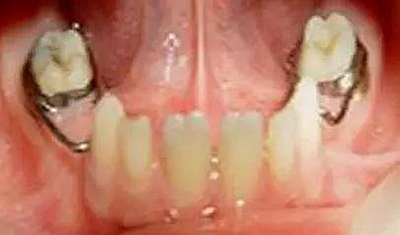

【牙醫(yī)干貨】各種間隙保持器賞析

③雙側(cè)乳磨牙早失,用其他間隙保持器裝置困難的病例。